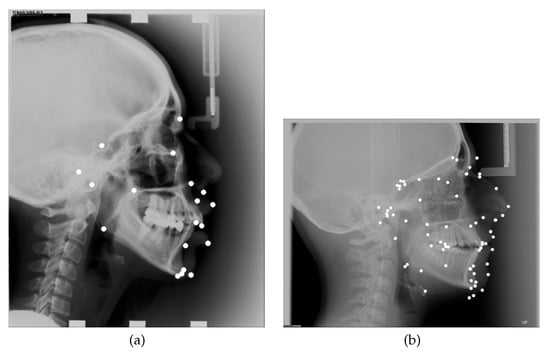

There exist lateral and frontal cephalograms. Lateral cephalograms provide a lateral view of the skull, while the frontal cephalograms present an antero-posterior view of the skull. The lateral cephalograms will be utilized in this study. Figure 1 depicts sample lateral cephalograms, captured in a natural head position, which enables the repeatability of image capture and comparison of different cephalometric analyses.

This database is divided into three sets. The first 300 out of 400 images are from the 2015 Automatic Cephalometric X-Ray Landmark Detection Challenge [4]. These 300 images were split into a training set (150 images) and testing set 1 (the remaining 150 images). The 2016 Automatic Cephalometric X-Ray Landmark Detection Challenge brought another 100 images to this public database. These 100 images are denoted as testing set 2. Figure 1a depicts a sample annotated image from this public database. Landmarks are actually pixels, but they are depicted as white circles in this image.

Seventy-two cephalometric landmarks were annotated on each image by a single experienced orthodontist. A list of all annotated landmarks is gathered in Table 2. Most landmarks are anatomic landmarks, while the rest were constructed relative to anatomic landmarks, or were defined as intersections of particular lines and/or planes, where lines/planes were defined by specific anatomic landmarks or skull structures. An example of a constructed landmark is RT-abo, which is lying on a silhouette, halfway between the landmarks articulare (Ar) and gonion (Go). Based on their expertise, AUDAX classified landmarks into five classes with respect to their importance in cephalometric analyses. The 38 most important landmarks (class 5) are highlighted in Table 2. On the other hand, AUDAX also classified the landmarks into five classes with respect to the difficulty of their determination. The six most difficult to determine landmarks (class 5) are underlined in Table 2. All 72 denoted landmarks were used as the ground truth in our research. Figure 1b depicts a sample image from this private database, with 72 annotated cephalometric landmarks.

Figure 1. Sample annotated cephalograms from (a) the ISBI public database [5], with 19 landmarks, and (b) the AUDAX private database, with 72 landmarks (white circles).